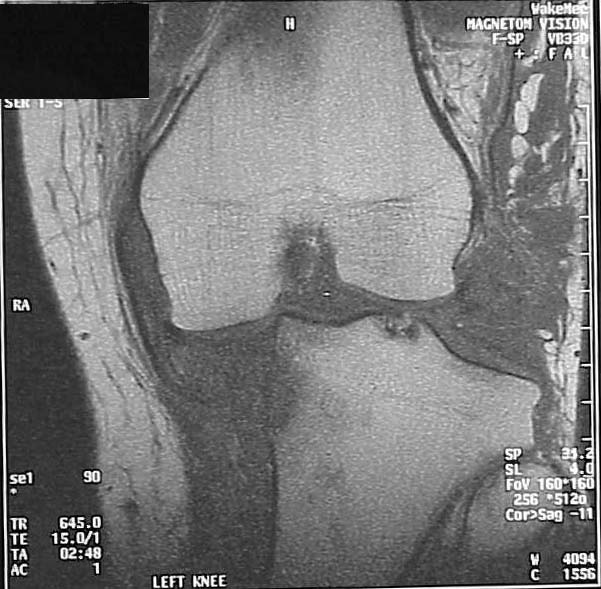

He had STSG and delayed ACL/PCL and posterolateral corner reconstruction at 3 weeks. I only have his injury films, but he says his leg always has appeared to be in varus. He has a sedentary job, painless ROM 0-100 degrees, walks w/ slight limp. He made an appointment to establish a new physician as his insurance has changed. His clinical appearance and current xrays are impressive, but he does not seem too concerned. Any thoughts on interventions? He is getting his post reconstruction xrays for review.

Lat 18 mos

Did he have a medial tibial plateau fracture with the injury , or has the medial plateau eroded as a result of his gross varus thrust? No postero-lateral reconstruction will stay intact in the presence of such gross genu varus,and the ACL and PCL recontructions must not be intact to allow such a degree of subluxation.

My assessment is that you have a young (23) patient with chronic severe subluxation of the knee joint and deformity 1.5 years after knee dislocation with failed ligamentous repairs of the ACL, PCL and PLC. His motion is surprisingly good (0-100) and his symptoms are surprisingly minimal. He is showing radiographic degeneration of the joint and also has peroneal palsy.